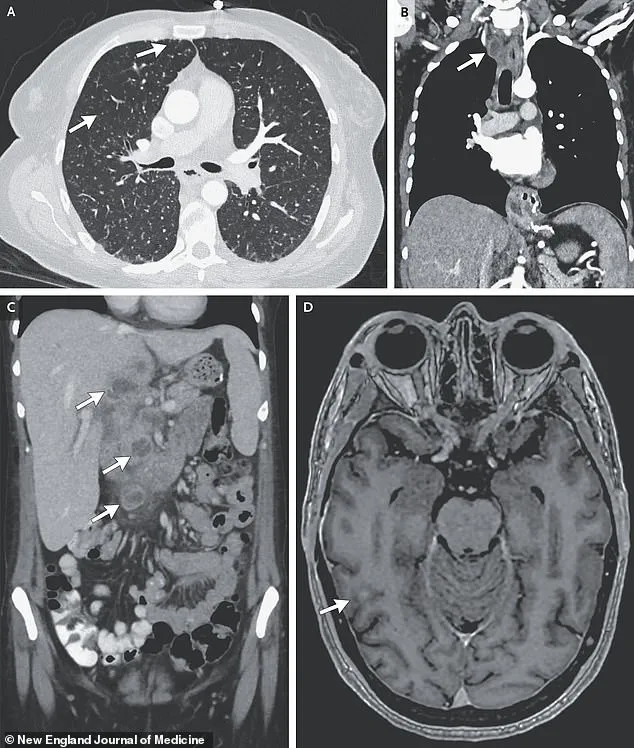

A harrowing case study illustrates the devastating consequences of undiagnosed and untreated TB.

A woman’s medical scans revealed nodules in multiple organs, including her lungs, liver, pancreas, and brain.

Her journey through the healthcare system was fraught with complications, including a 33-day hospitalization for antibiotics, steroids, and antiretroviral therapy to combat HIV.